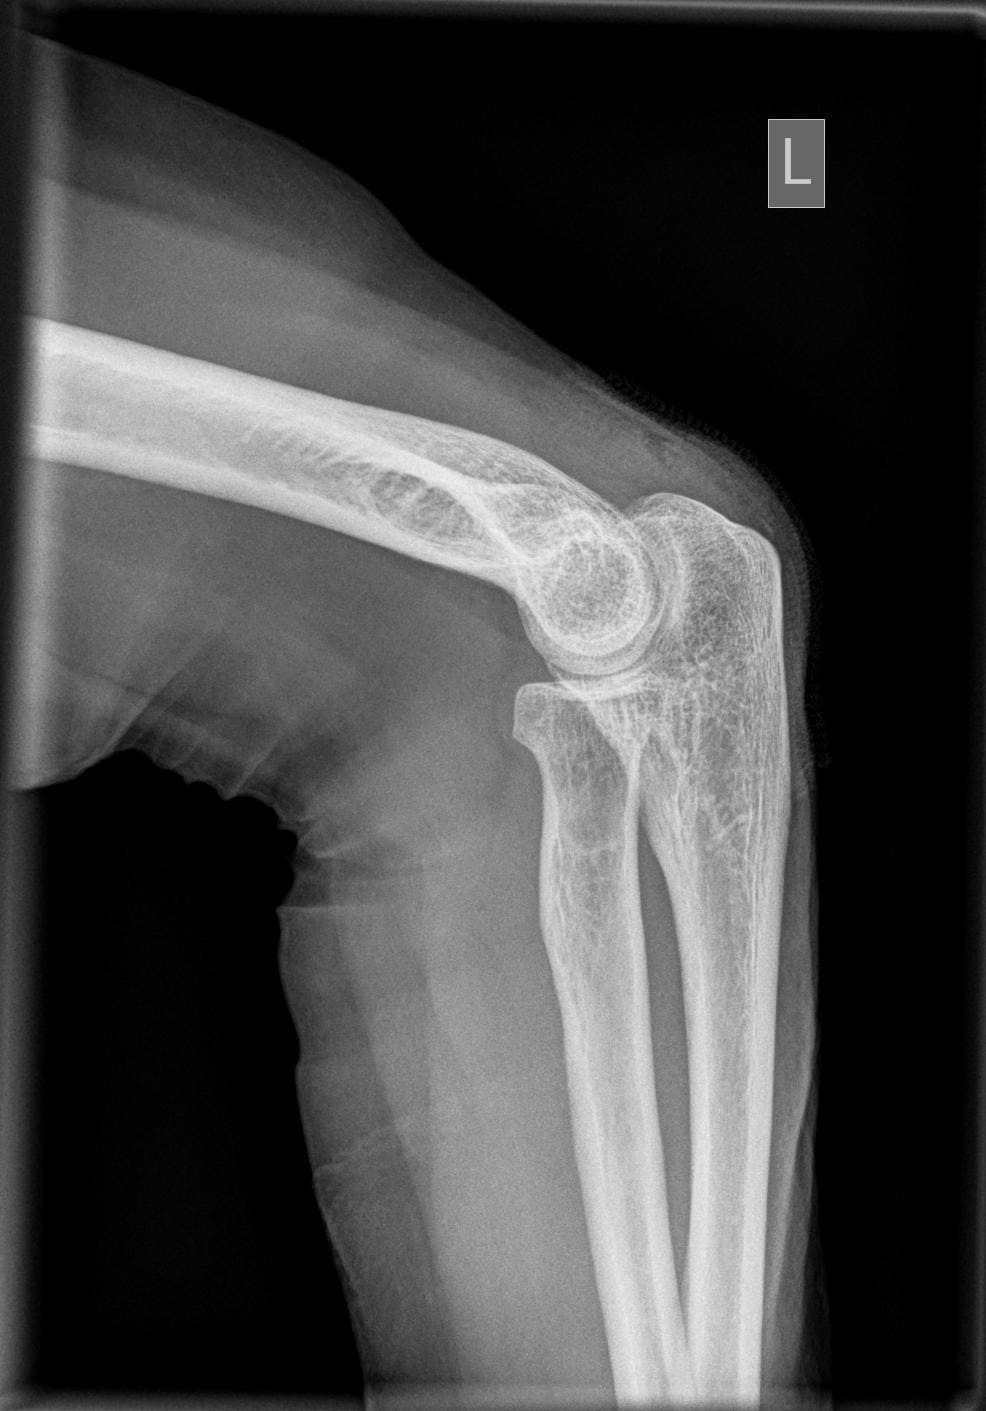

Ellenbogen a.p.

11_2.jpg

Fehler

Der Gelenkspalt zwischen Humerus und Radiusköpfchen ist nicht frei; die Gelenkfläche des Radiusköpfchen ist stark oval gezeichnet und verdeckt die Gelenkfläche des Humerus. Der Patient kippte den Vorderarm mit der Hand hoch statt sie flach aufzulegen.

Abhilfe

Es müssen Vorder- und Oberarm streng gestreckt gehalten werden.